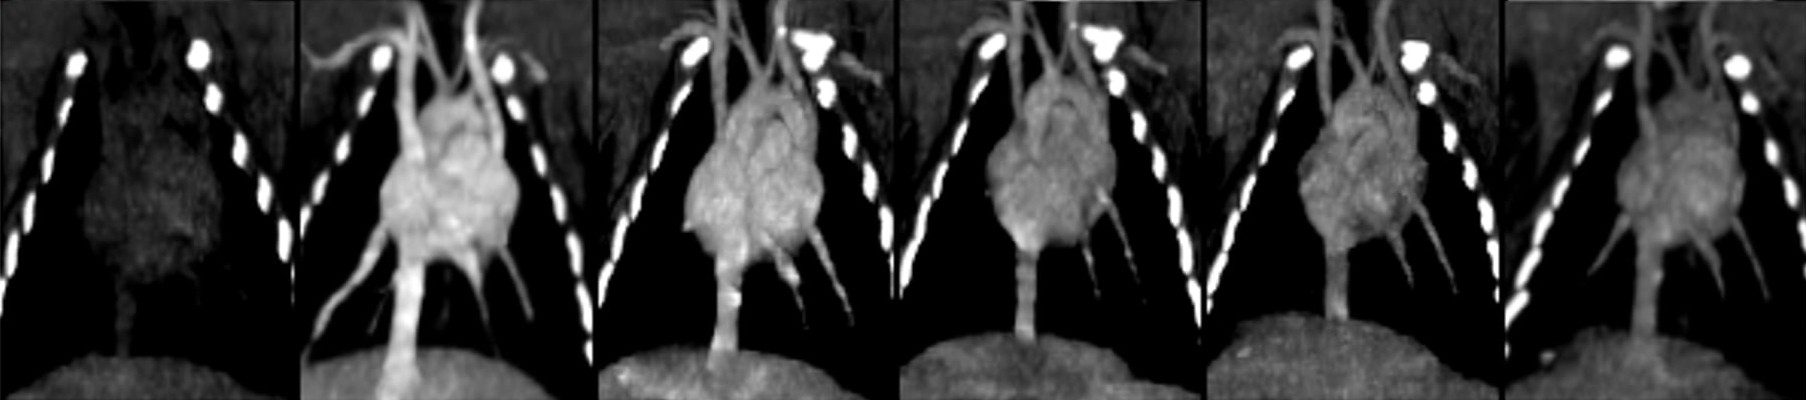

A non-iodinated 'blood-pool' agent that remains in the vascular system for minutes, enabling unprecedented interrogation of blood vessels and the liver.

+ Extended Imaging Window

Vivid, prolonged, full-vascular enhancement

Conventional Iodine

Poor and inconsistent opacification with rapid washout